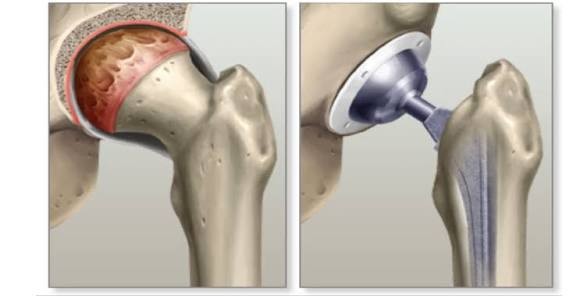

A total hip replacement (THR), also known as total hip arthroplasty, is a common surgical procedure in which damaged surfaces of the hip joint are replaced with artificial components made of metal, ceramic, or plastic. The surgery is performed to relieve pain, reduce stiffness, and improve mobility, most often due to severe arthritis or injury.

The procedure involves removing the damaged hip joint and inserting a new stem and ball into the thigh bone (femur), along with a new cup into the pelvis (acetabulum). Recovery includes structured physical therapy over several months.

- A surgical procedure to replace damaged bone and cartilage in the hip joint with artificial components.

- Both the ball (head of the femur) and the socket (acetabulum of the pelvis) are replaced.

- Removal: The damaged femoral head (ball) is removed.

- Femur Implant: A metal stem is inserted into the hollow femur, topped with a metal or ceramic ball.

- Socket Implant: Damaged cartilage is removed, and a new cup (plastic, metal, or ceramic) is placed into the pelvis.

- Spacer: A plastic or ceramic liner is inserted between the new ball and socket for smooth movement.